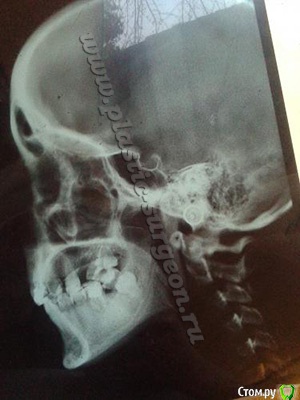

кристина1877 Опубликовано 12 июня, 2015 Поделиться Опубликовано 12 июня, 2015 Скажите пожалуйста, брекет-система поможет выдвинуть ниж чел вперед и улучшить профиль губ? или придется прибегнуть к операции?? и еще, у меня мелкое преддверие. обязательно ли делать перед постановкой брекетов вестибулопластику? Ссылка на комментарий